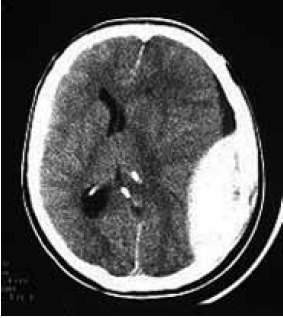

Homem de 43 anos dá entrada na emergência consciente e orientado, apresentando ferimento lacerocontuso em região parietal esquerda após sofrer queda da própria altura. Trazido pelo SAMU 192 (suporte básico) ao hospital, relatou que estava se sentindo bem, mas que não lembrava do que havia acontecido. Duas horas após sua admissão, enquanto aguardava realização de exames, o paciente perdeu a consciência. Na reavaliação do paciente, abertura ocular aos estímulos dolorosos, resposta verbal com sons incompreensíveis e resposta motora com reflexo de retirada; pupilas anisocóricas. Tomografia de crânio demonstrada.

Qual o provável diagnóstico e a topografia anatômica da lesão?